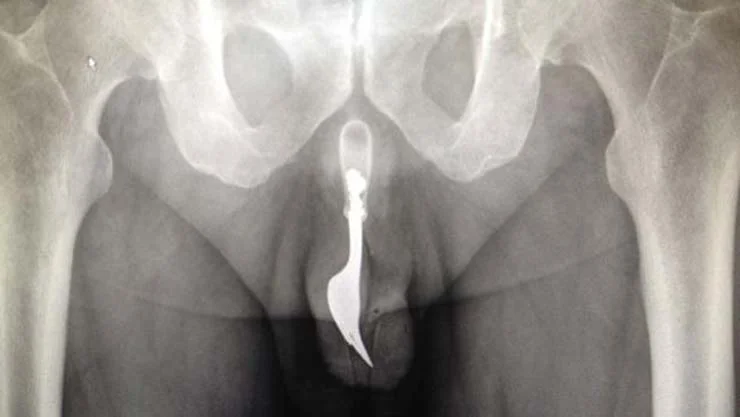

Penis

• “CARVED DOWN PIECE OF DOMINO INCISED PENIS INSERTED DOMINO PIECE INTO PENIS NOW WANTS IT REMOVED”

• SANDAL BUCKLE

• BB

• DOLL SHOE

• “HAD PEBBLE STUCK IN PENIS WHILE SWIMMING IN A LAKE 3 WEEKS AGO”

• PEN CAP

• PEN

• 3 INCH STRAIGHT PIN

• “MARBLE IN PENIS, CUT PENIS TRYING TO GET IT OUT”